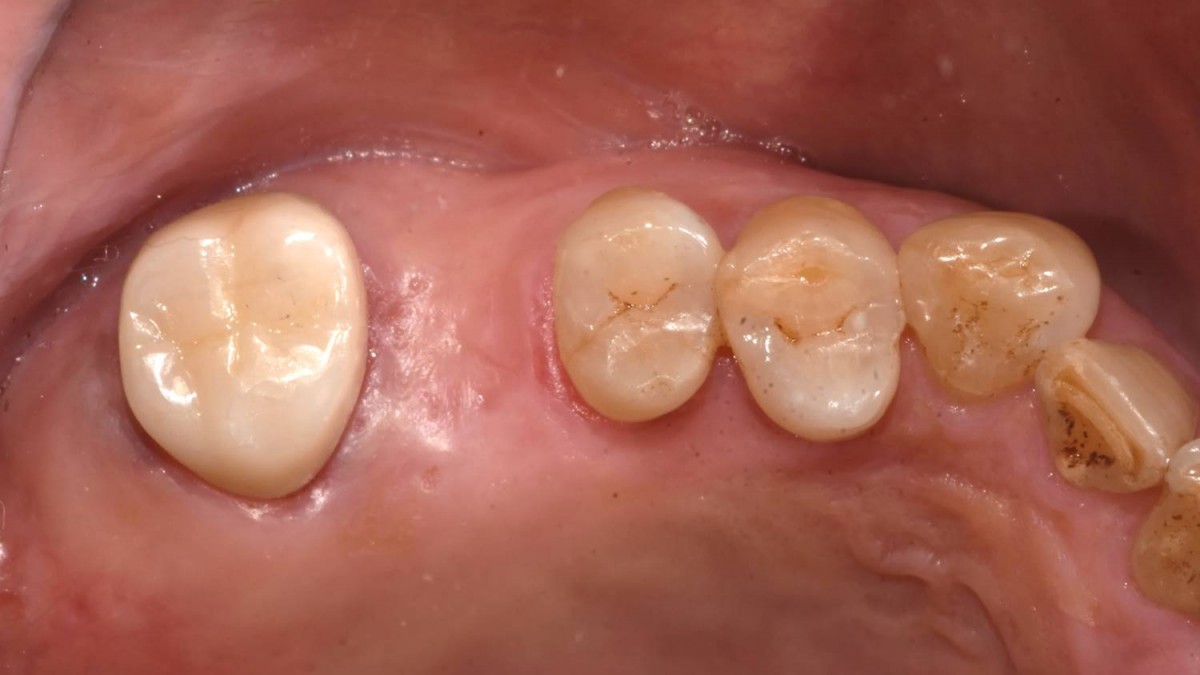

Maxillary Sinus Graft, 2 Implants, Crown Contouring

<GCaks> A 56-year-old male patient had pain-inducing caries, and perio-involved tooth mobility resulted in a tooth fracture at 1st molar. And it was removed months ago. He was a heavy smoker and showed poor oral hygiene.